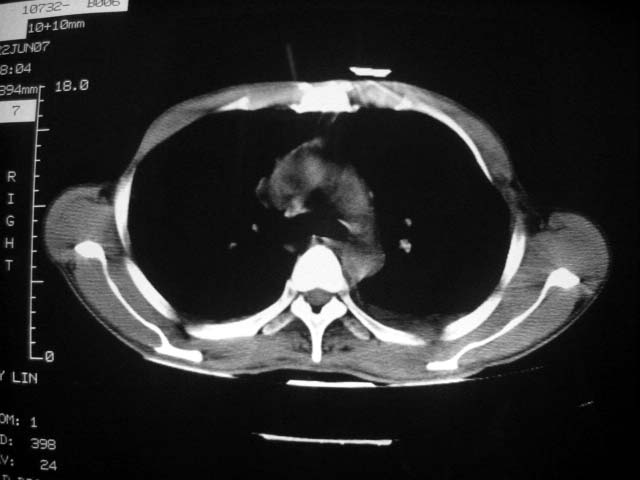

患者现无咳嗽咳痰及咳血,肝功好转,血清白蛋白降低,球蛋白升高,白球比小于0.5.少量腹水。

根据前后片比较应该考虑迁徙性肺脓肿,回帖相差甚远是因为前后片变化太大出乎大家意料之外,这就是影象诊断要结合临床复查对比的必要性,

患者近期复查胸ct正常,轻度肝功异常,保肝、抗病毒(拉美夫叮)治疗中。